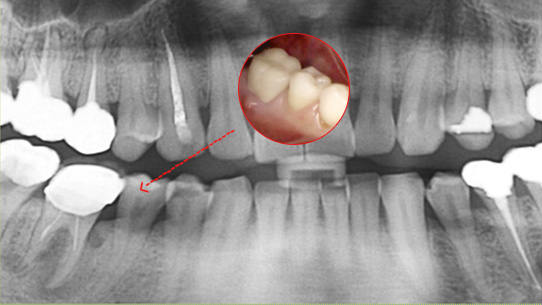

심한 염증으로 치조골이 광범위하게 소실, 아래쪽 신경관이 가까이 있어 치근단수술이 불가능한 상태, 타 병원에서 임플란트 진단을 받았지만,

고운미소치과에서 치아를 발치하고 뿌리 쪽 염증을 제거한 후 발치한 치아를 다시 심는 치아재식술을 시행하였습니다.

기존 신경치료 부위에 염증과 치조골이 소실되고 있는 상태

치아를 발치하고 염증을 제거, MTA로 충전하고 치아를 다시 심음. (난이도 중)